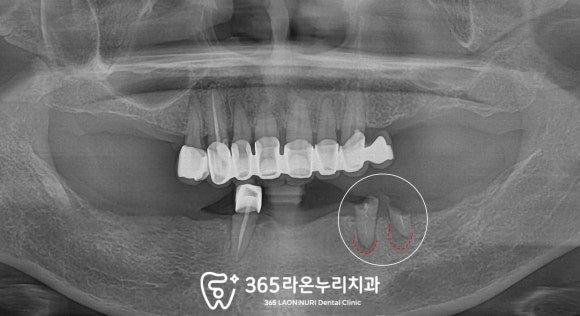

오늘 오산 신장동 치과 에서 소개해드릴 환자는

이전에 제가 진료했던 케이스 중에서

꽤 많은 정성을 들였던 사례인데요,

위아래 치아가 없는 부분을 대신하기 위해

틀니(덴처,denture)를 사용하다보니

그로인한 불편감을 호소하고 계셨으며

임플란트를 해야되는 곳이

여러군데 있는 것 같다며

상담을 위해 찾아오셨던 환자였습니다.

다른 각도로 살펴보면

상악은 어금니 부근이 결손된

부분 무치악 상태였고

하악은 치관이 부러져서

뿌리만 남은 채로 잇몸에 박혀있는 곳도 보이네요.

아마 남은 자연치에 덴처를 걸어 사용하다보니

이제는 수명을 다해

이가 부러진 것 같습니다.

파노라마 엑스레이를 찍어

조금 더 자세히 살펴봤는데요,

부러진 치근 끝에 일부 염증 소견도 보이니

하루빨리 문제 해결이 필요할 것 같네요.